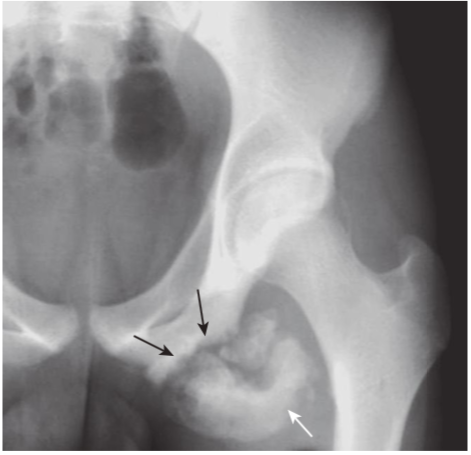

Healing avulsion fracture of ischial tuberosity.

Avulsion fractures of the pelvis occur in anatomically predictable locations (tendons insert on bones in known locations), and they are typically small fragments. Sometimes they heal with such exuberant callus formation that they can be mistaken for a bone tumor. There is a healing fracture (black arrows)of the ischial tuberos- ity caused by contraction of the hamstring muscles. There is a great deal of external callus present (white arrow).